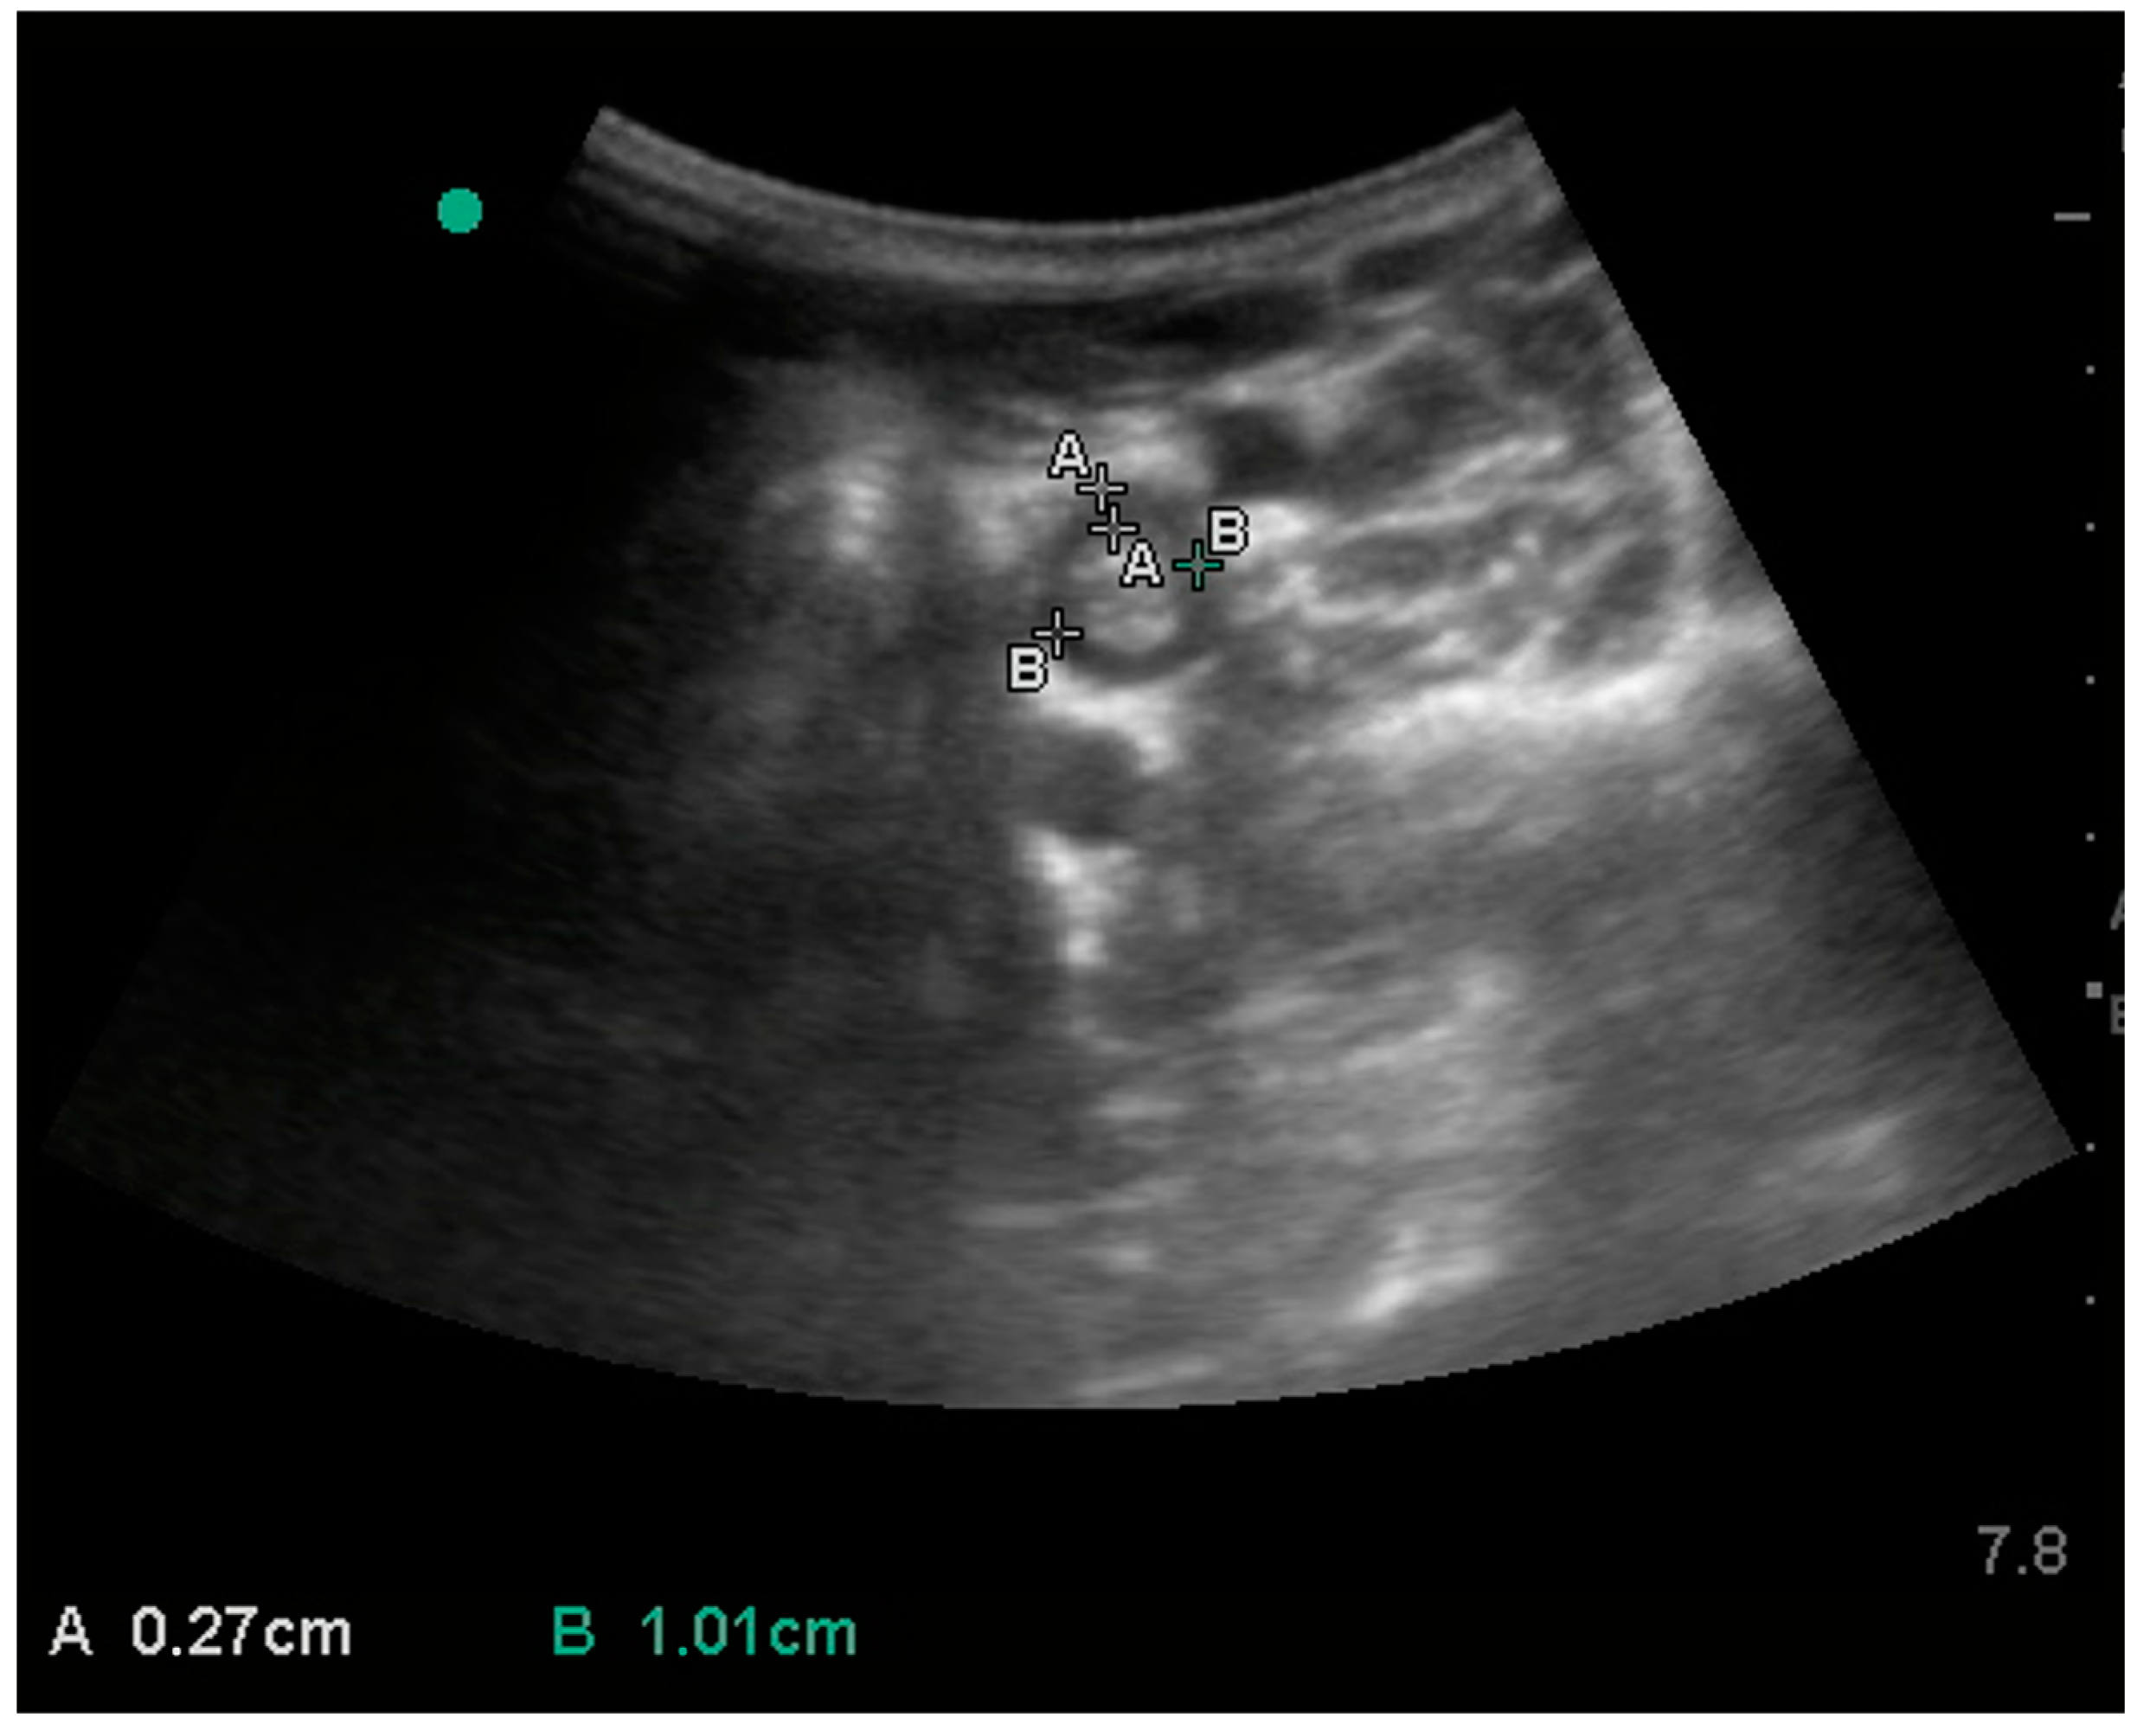

3. Results

| Stomach | wall thickness | 6.6 (1.1) | 5.5–6.7 | 5.6 | 5.7 | 7.0 | 8.2 | 5.2 | 9.1 | 3.9 |

| Duodenum | wall thickness | 3.5 (0.6) | 3.1–3.7 | 3.0 | 3.3 | 3.8 | 4.0 | 2.2 | 5.3 | 3.1 |